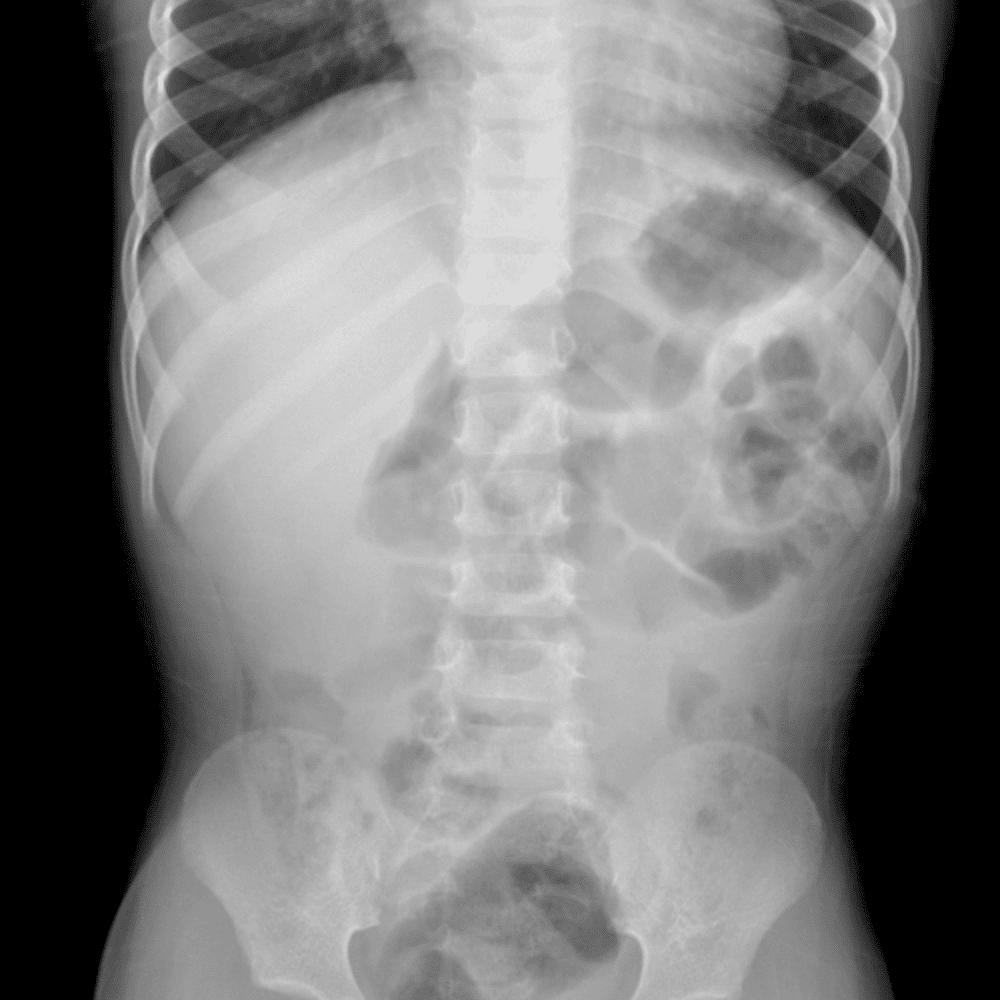

Peds Abdomen

Practice

Simulates call by including subtle or difficult cases and some normals.

30 cases